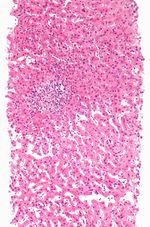

نناقش أدناه الأنماط النسيجية المرضية المحددة لإصابة الكبد من التلف الناجم عن المخدرات.

نخر منطقي

هذا هو النوع الأكثر شيوعًا من نخر خلايا الكبد الناجم عن الأدوية حيث تكون الإصابة محصورة إلى حد كبير في منطقة معينة من فصيص الكبد . قد يظهر على شكل مستوى مرتفع جدًا من ناقلة أمين الألانين واضطراب شديد في وظائف الكبد مما يؤدي إلى فشل الكبد الحاد .

- تشمل الأسباب:

- پاراسيتامول, رابع كلوريد الكربون

في هذا النمط ، يرتبط نخر الخلايا الكبدية بترشح الخلايا الالتهابية. يمكن أن يكون هناك ثلاثة أنواع من التهاب الكبد الناجم عن الأدوية. (أ) التهاب الكبد الفيروسي هو الأكثر شيوعًا ، حيث تتشابه السمات النسيجية مع التهاب الكبد الفيروسي الحاد. (ب) في التهاب الكبد البؤري أو غير النوعي ، قد تصاحب البؤر المتناثرة لنخر الخلية تسلل الخلايا اللمفاوية . (ج) التهاب الكبد المزمن يشبه إلى حد بعيد التهاب الكبد المناعي سريرياً ومصليًا ونسيجيًا.

- الأسباب:

- التهاب الكبد الفيروسي أ: هالوثان, أيزونيازيد, فنيتوين

- التهاب الكبد البؤري ب: الأسپرين

- التهاب الكبد المزمن ج: ميثيلدوپا, ديكلوفناك